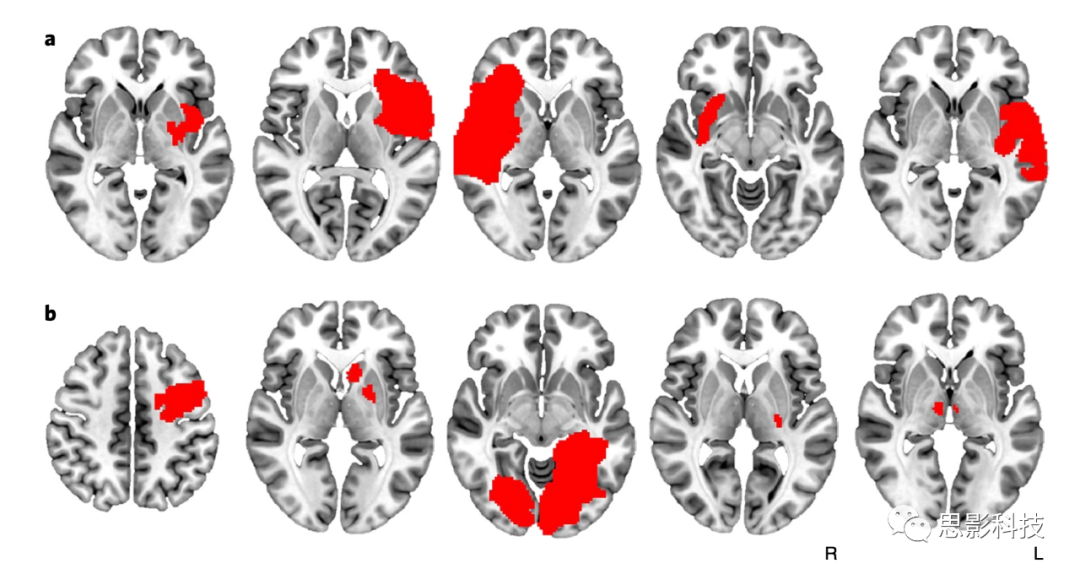

通過兩個獨立的數據庫(見補充材料表1),我們找到了129名有獲得性腦損傷且每天吸煙的患者,這些患者中:69名患者(53%)繼續(xù)吸煙;34名患者(26%)滿足成癮緩解的條件(病變后立即戒煙,不會復發(fā)且戒煙后沒有煙癮)。平均來看,病人平均每天吸23.1s.d.=14.1)支煙;煙癮得到緩解的患者與未戒煙的患者之間差異不大(P=0.98)。病變區(qū)域存在高度異質性(如圖1及補充材料圖1所示)。標準體素損傷癥狀映射(voxel-wise lesion-symptom mapping, VLSM)未能識別任何與成癮緩解顯著相關的體素(P>0.2,也未能顯示兩個病變組之間的一致性(空間相似性r=0.05; 置換檢驗P=0.38),此外,也未能將不同隊列間的成癮性關聯起來(P=0.36)(見補充材料圖2)。

1:與成癮緩解相關的病變發(fā)生在許多不同的大腦位置。一些與吸煙成癮緩解相關的病變與島葉相交(a),但許多其他病變則沒有(b)。每個切片代表不同的患者,病變位置以紅色顯示。所有129例患者的病變如補充材料圖1所示。

S1:吸煙者隊列病變。導致吸煙成癮緩解的病變(A,n = 34)。未戒煙患者的病變(B,n = 69)。戒煙但未緩解的患者的病變(Cn = 26)。每個切片代表不同的患者。組間的病變大小沒有差異(單因素方差分析,F = 1.78p = 0.17)。